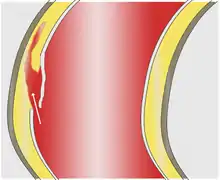

La dissection débute par une « porte d'entrée », rupture de la paroi interne (intima) permettant le décollement de cette dernière en pleine media (partie moyenne de la paroi). Ce décollement s'étend le plus souvent d'amont en aval et forme une poche de sang circulant, le « faux chenal », séparé du « vrai chenal » (la lumière de l'artère) par un flap (constitué par la paroi décollée). Plus rarement, la progression se fait en rétrograde : d'aval en amont (un tiers des cas[11]). La porte d'entrée peut être multiple dans un quart des cas[12].